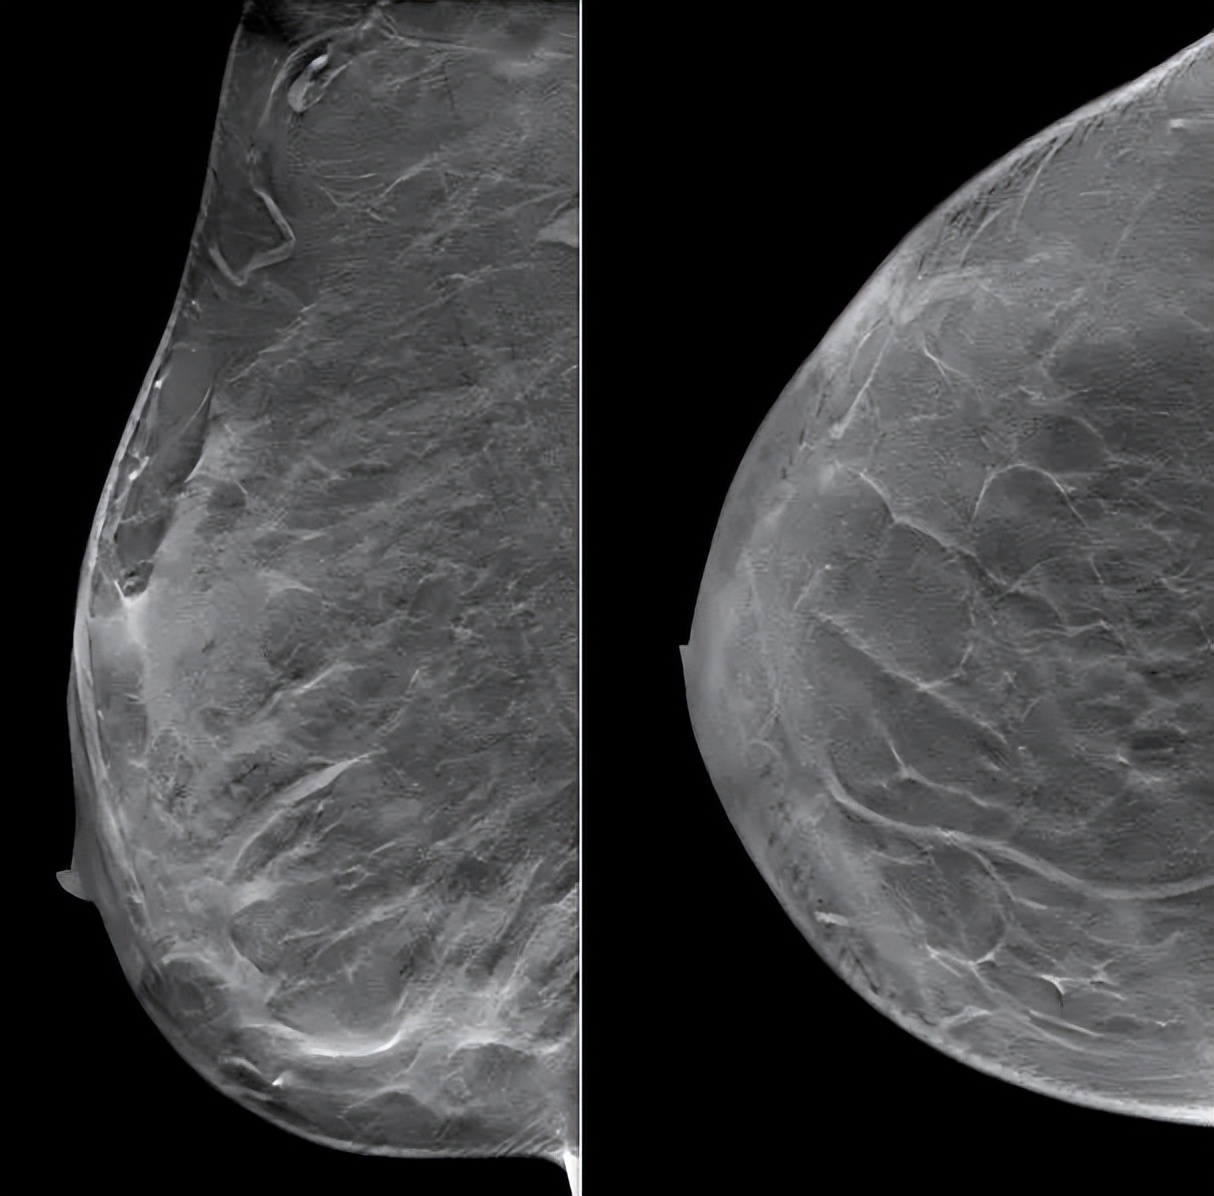

(3 cycle 后)2021.9.21 钼靶示:右乳外上象限不规则形肿块明显缩小,右腋窝淋巴结亦较前缩小。

图6. 钼靶

▌临床疗效评价PR:

患者由于化疗后出现Ⅳ骨髓抑制,拒绝继续新辅助化疗,要求手术治疗,遂于2021.9.23行右乳癌改良根治术。